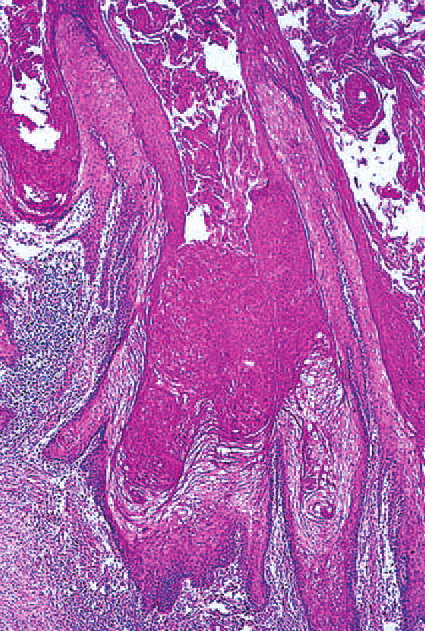

Verrucous scc =الكارسينوما الشائكة الخلايا الثؤلولية